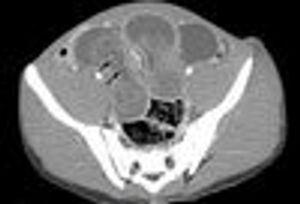

Intussusception: A Challenging Diagnosis in AdolescencePublished: December 21st 2011 | Updated: